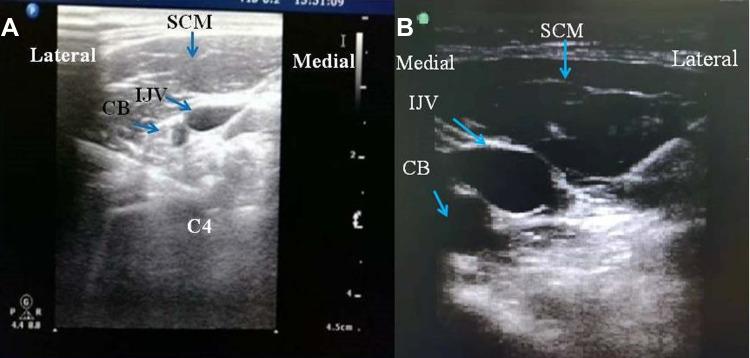

Forty-eight ASA III-IV patients with hyperparathyroidism secondary to renal failure were included: 24 patients received ultrasound-guided bilateral superficial and deep cervical plexus block combined with general anesthesia (group A), and 24 patients received general anesthesia alone (group B). Postoperative patient-controlled intravenous analgesia was provided with sufentanil 2 μg/kg. The primary outcome is the postoperative pain scores. Secondary outcomes include intraoperative remifentanil dosage, changes in hemodynamics, extubation time, and sufentanil consumption. Surgical outcomes regarding calcium, phosphorus and parathormone values were also noted.

Ultrasound-guided bilateral superficial and deep cervical plexus block combined with general anesthesia for TPTA is an effective strategy to improve anesthesia management and achieve better postoperative analgesia, and has no impact on surgical outcomes.